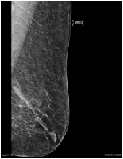

Invasive Ductal Carcinoma in the Setting of Mammary Duct Ectasia

Sarit Sandowski Pizow1,Bradley Gluck2,Alan Heimann3, Edna Kapenhas4*